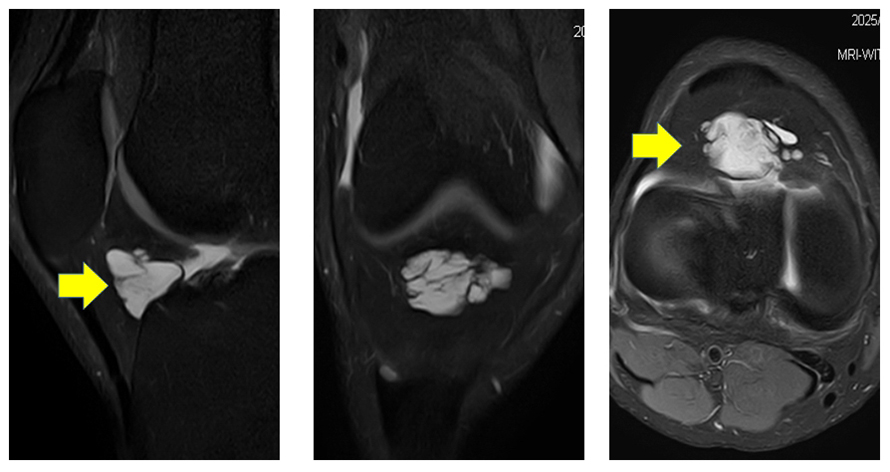

另一位34 歲男性因右膝前中線壓痛求診骨科門診,初步X光檢查也無明顯異常發現。進一步磁振造影檢查則發現於右側膝蓋髕骨下脂肪墊下方有一群囊腫樣病灶聚集,周邊有少量關節腔積水及組織水腫。同樣的其他膝蓋重要韌帶、肌腱及半月板等結構沒有明顯異常。依照影像發現及臨床症狀也判定為因腱鞘囊腫引起的髕骨下脂肪墊症候群。(如圖 B)

圖 B 右膝 髕骨下方脂肪墊下有一群囊腫樣病灶聚集(黃色箭頭)